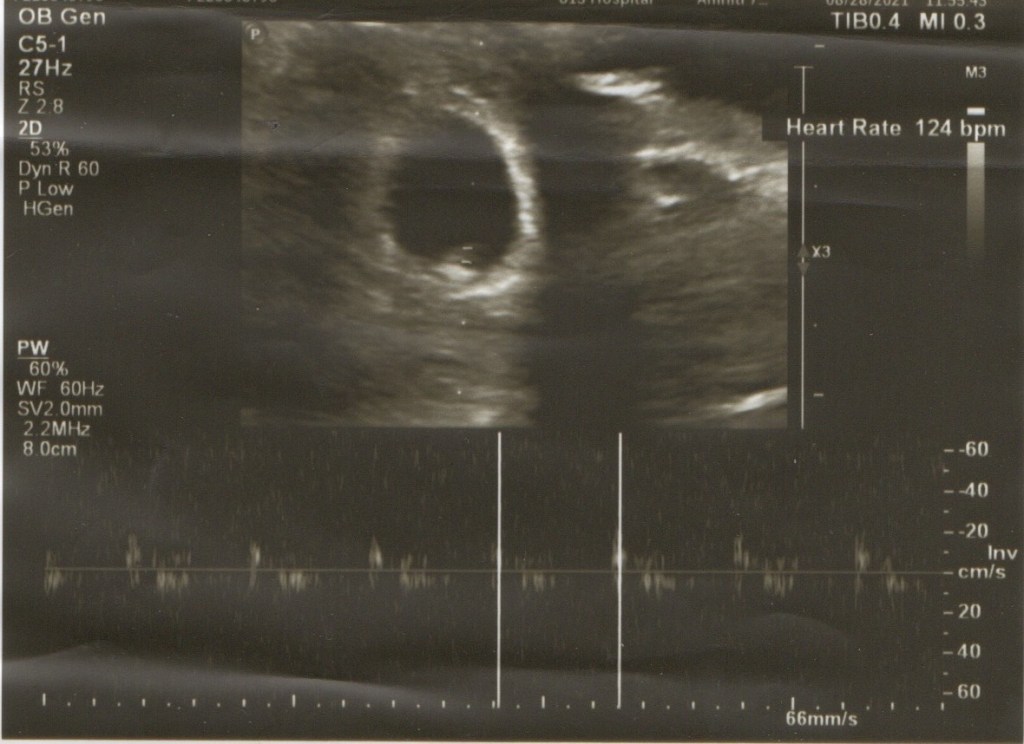

醫生很仔細的幫我們照了腹部超音波,說著床位置跟妊娠囊大小都很正常,一切都很好,不用擔心,量了一下尺寸,沒想到推估是已經7週了,差一點就可以直接拿孕婦加值手冊,可惜下週還要再來一次,不過可以再照一次超音波也是不錯。